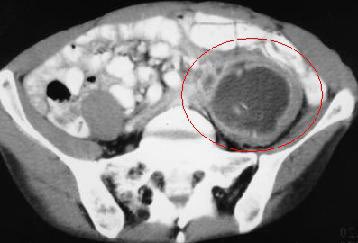

كما لا تقل الاشعة مثل المقطعية اهمية عن باقي الفحوصات في الكشف عن وجود اي مضاعفات للمرض لا سمح الله خصوصا في الحالات التي تحضر لقسم الطواريء. من المضاعفات التي يمكن حدوثها: وجود تجمع صديد داخل البطن (خرّاج)، ثقب في القولون، انسداد في الامعاء، و غيرها مما يستلزم تدخل جراحي.